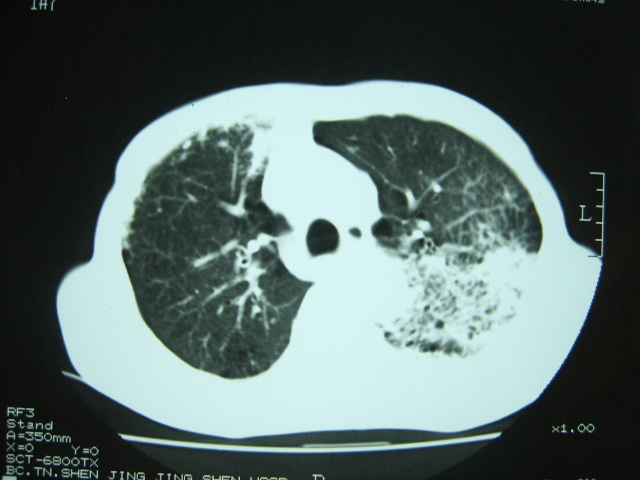

男74岁,咳嗽,寒战,低烧。有糖尿病史。

考虑:1、左下肺脓肿;

2、双肺结核。

考虑:1、左下肺脓肿;不排除霉菌感染

1、左下肺肺脓肿,合并霉菌球形成?.2、双肺陈旧性病灶.3、右上肺病灶警惕瘢痕癌,建议定期复查.

两肺结核,左下肺大片实变,内见空洞性病变,壁不规则,结合糖尿病史,考虑:结核性?霉菌性?建议结合实验室检查或治疗后复查。